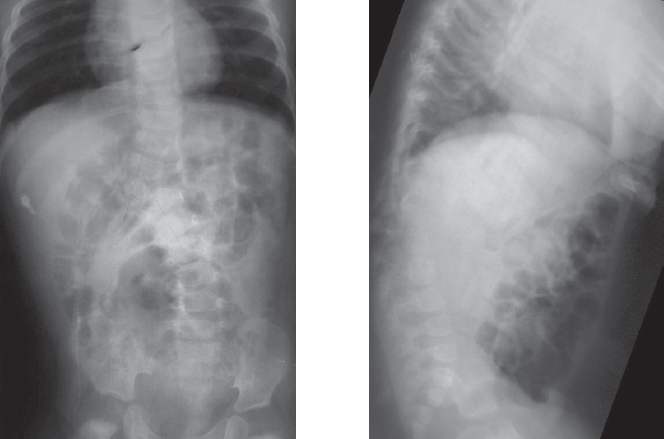

Неврологического дефицита нет (Frankel E). При магнитно-резонансной томографии данных за компрессионную миелопатию не получено. При компьютерной томографии (рис. 1) определить природу порока развития затруднительно в связи с выраженными вторичными изменениями смежных сегментов. Для анализа представлены рентгенограммы, выполненные в раннем возрасте (5 месяцев, 1 год 7 месяцев; рис. 2, 3).

Рис. 1. Компьютерная томография при обращении (возраст 12 лет)